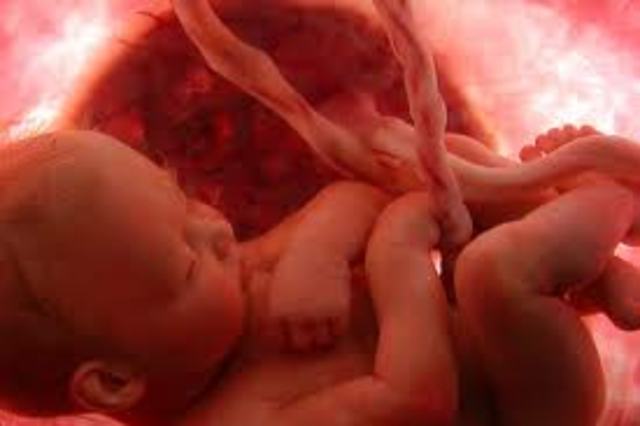

• End of Third Month

End of Third Month

• Babys starts hearing

Babys starts hearing

Tiny bones in your fetus's ears are making it that the baby can hear your voice when you're speaking. The baby starts hearing around the sixteenth week of pregnancy.

• End of Fourth Month

End of Fourth Month

• End of Fifth Month

End of Fifth Month